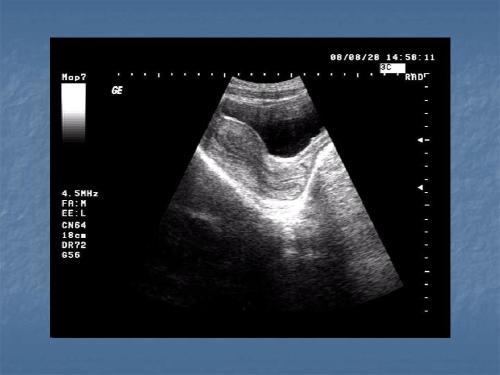

彩超诊断肝脏病变,主要是通过回声呈现出来的不同特点,而回声特征上早期肝硬化、弥漫性肝纤维化与脂肪肝有一定相似度,缺乏特异性。但是除了肝纤维化和肝硬化,彩超还可以观察肝脏的结构、形态、供血等,能够发现囊肿、血管瘤、钙化灶等占位性病灶。